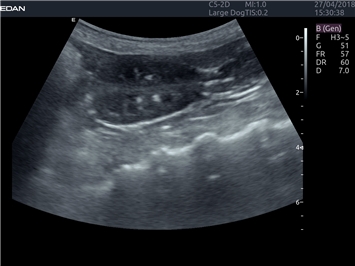

EDAN Acclarix LX4 VET

EDAN Acclarix LX4 VET представляет собой профессиональную ультразвуковую систему, специально разработанную для ветеринарных исследований. Сочетание стабильности, высокой производительности и эффективности делает эту систему идеальным выбором для современной ветеринарной практики.

• Универсальные датчики для различных видов животных

• Специализированные предустановки для ветеринарных исследований